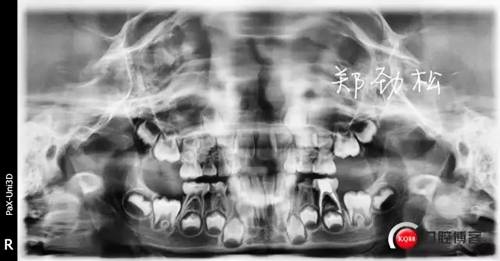

我的病例三 7E牙髓炎

836605.jpg

297418.jpg